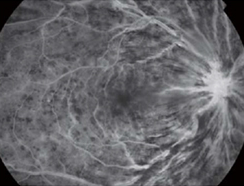

網膜中心静脈閉塞症 -

網膜静脈分枝閉塞症

フルオレセインという蛍光色素の入った造影剤を腕の静脈から注入し、眼底カメラで網膜の血管を観察します。

血管の形状、血管からの漏出、網膜の虚血などがわかります。